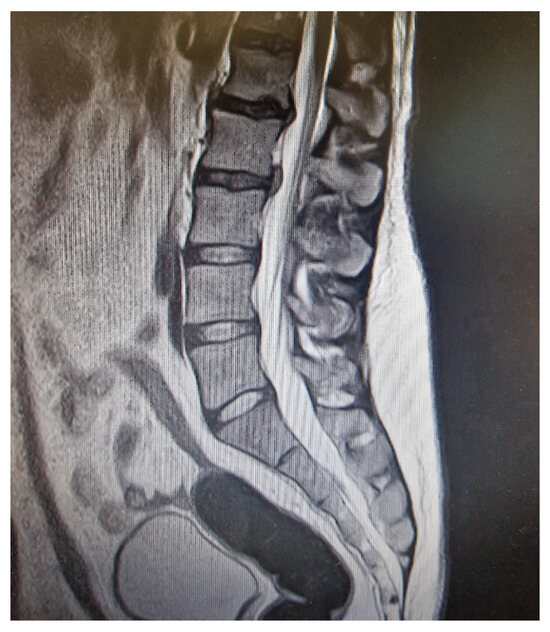

- MRI findings can be non-specific, particularly when performed after the initiation of therapy, highlighting the importance of early imaging and a strong clinical suspicion.